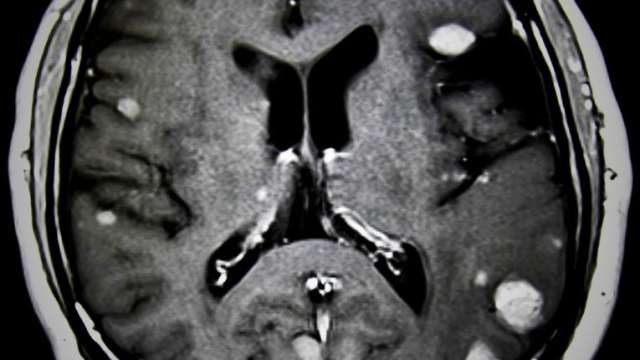

Brain Metastases

At UCLA, Radiation therapy is an important tool to relieve the symptoms associated with metastatic cancer.